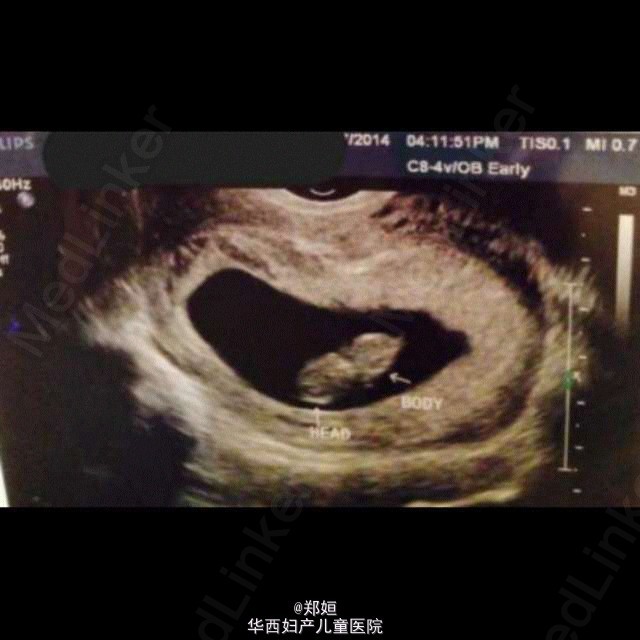

孕早期B超示胎儿图像

最近看到的一个病例,跟大家分享